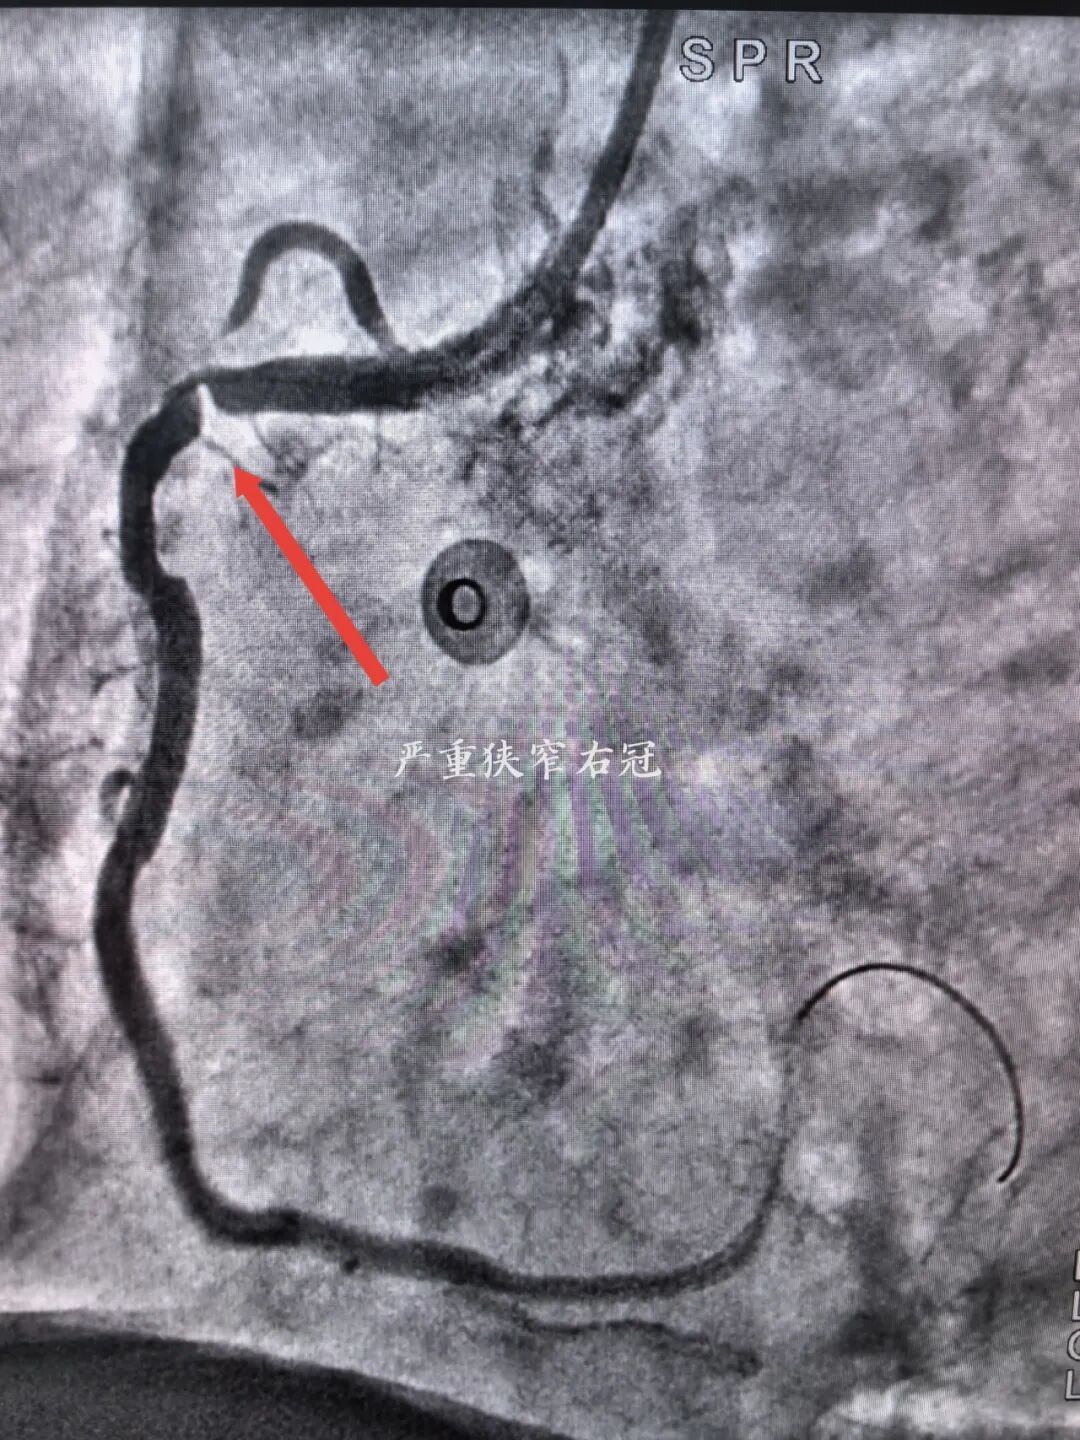

入院完善各项检查后考虑为冠心病合并右锁骨下动脉狭窄可能,经宋坤青主任团队研究后,决定为该患者施行冠脉造影+锁骨下动脉造影。经过严谨的术前讨论及充分的术前准备后,在2024年06月07日上午,宋坤青主任、赵博韬副主任及杨亚楠、冉德聪主治医师为该患者进行了造影手术,结果提示右冠状动脉近近段90%狭窄,前降支近中段90%狭窄,右侧锁骨下动脉闭塞。

右冠状动脉严重狭窄